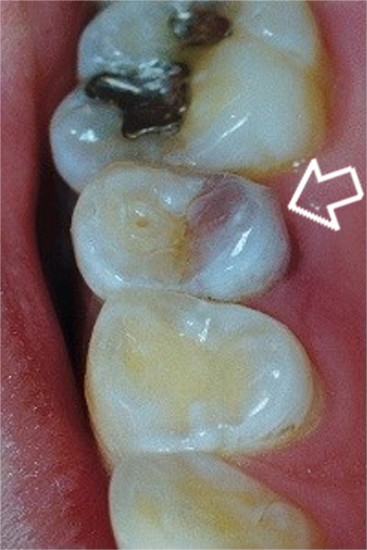

Necrotic Tooth (a tooth which has died)